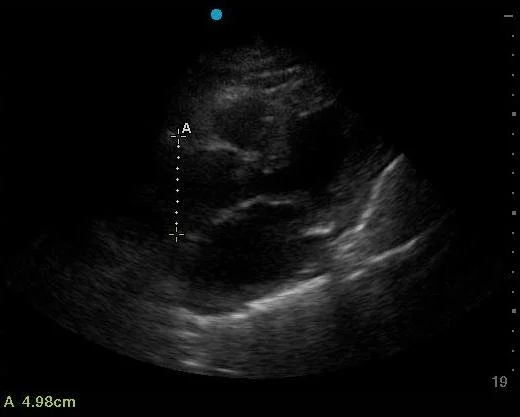

The first clip shows a very dilated aortic root, as measured 4.98cm (>4cm is considered abnormal for the thoracic aorta/aortic root).

• A dilated aortic root/thoracic aorta >4cm.